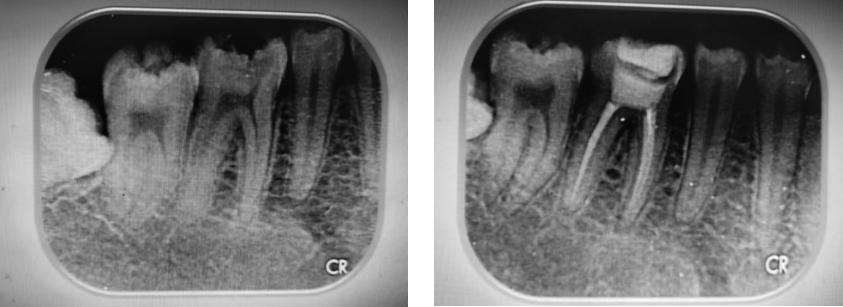

• 新型生物陶瓷iRoot SP联合单尖充填技术治疗慢性根尖周炎的临床效果

2025, 35(14):78-84. DOI: 10.3969/j.issn.1005-8982.2025.14.014

摘要 (283) HTML (310) PDF 769.00 K (95) 评论 (0) 收藏

摘要:目的 比较AH-Plus根管封闭剂结合热牙胶垂直加压充填技术与新型生物陶瓷iRoot SP联合单尖充填技术在慢性根尖周炎治疗中的临床效果。方法 选取2020年5月—2023年5月宝鸡市人民医院口腔科收治的慢性根尖周炎患者76例,按照随机数字表法分为对照组、观察组,各38例。对照组采用AH-Plus根管封闭剂结合热牙胶垂直加压充填技术,观察组采用新型生物陶瓷iRoot SP联合单尖充填技术。分别收集患者治疗前(T0)、治疗3个月(T1)、治疗6个月(T2)的龈沟液检测炎症因子水平。统计并比较两组患者根管充填时间、治疗充填质量与疗效。采用视觉模拟评分法(VAS)评估患者治疗各时期疼痛情况。统计两组患者治疗各时期咀嚼功能、咬合功能,采用电测牙髓试验(EPT)评估牙髓活性。采用根尖周指数(PAI)对患者X射线检查进行病损评估。结果 对照组充填时间长于观察组(P <0.05),超填比例高于观察组(P <0.05),显效/有效占比低于观察组(P <0.05)。观察组与对照组T1、T2时VAS评分比较,结果 ①不同时间点VAS评分比较,差异有统计学意义(P <0.05);②观察组与对照组VAS评分比较,差异有统计学意义(P <0.05);③两组VAS评分变化趋势比较,差异无统计学意义(P >0.05)。观察组与对照组T0,T1、T2时IL-1β、IL-6、IL-8、TNF-α水平比较,结果 ①不同时间点IL-1β、IL-6、IL-8、TNF-α水平比较,差异均有统计学意义(P <0.05);②观察组与对照组IL-1β、IL-6、IL-8、TNF-α水平比较,差异均有统计学意义(P <0.05);③两组IL-1β、IL-6、IL-8、TNF-α水平变化趋势比较,差异均有统计学意义(P <0.05)。观察组与对照组T0、T1、T2时EPT、咀嚼功能、咬合功能评分比较,结果 ①不同时间点EPT、咀嚼功能、咬合功能评分比较,差异均有统计学意义(P <0.05);②观察组与对照组EPT、咀嚼功能、咬合功能评分比较,差异均有统计学意义(P <0.05);③两组EPT、咀嚼功能、咬合功能评分变化趋势比较,差异均有统计学意义(P <0.05)。观察组与对照组T0、T1、T2时PAI评分比较,结果 ①不同时间点PAI评分比较,差异有统计学意义(P <0.05);②观察组与对照组PAI评分比较,差异有统计学意义(P <0.05);③两组PAI评分变化趋势比较,差异无统计学意义(P >0.05)。结论 iRoot SP联合单尖充填技术治疗慢性根尖周炎能够显著缩短治疗时间,有效控制治疗后疼痛,并在根尖区病损治疗及充填质量上展现出更佳的效果。